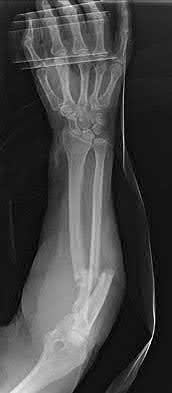

A 25-year-old female is involved in a motor vehicle collision. She presents with the isolated injury seen in Figures A through D. Her leg is swollen but her skin is intact. She has no clinical signs of compartment syndrome. Which of the following treatment options will allow for maintenance of fracture alignment and minimize the risk of soft tissue complications?

The patient presents with a closed distal third metaphyseal-diaphyseal distal tibia fracture with simple intra-articular extension. Immediate intramedullary nailing along with percutaneous fixation of the articular component provides appropriate restoration of length, rotation and alignment and minimizes the risk of wound complication.

Displaced distal third tibia fractures may be associated with simple intraarticular extension. Operative treatment of intra-articular distal tibia fractures has historically been performed with open reduction and internal fixation. Early open reduction and plate fixation of pilon fractures has been associated with high rates of infection and wound complication. In select patterns with simple articular extension, percutaneous screw fixation and medullary nailing may provide appropriate reduction with minimal soft-tissue risk.

Figures A and B demonstrate a distal third tibial shaft fracture with simple intra-articular extension. The axial and coronal CT cuts in Figures C and D further clarify the articular injury. Illustrations A and B demonstrate a comminuted distal third tibial fracture with simple intra-articular extension. Illustrations C and D are fluoroscopic images of the same injury after intramedullary nailing and percutaneous fixation of the articular component.